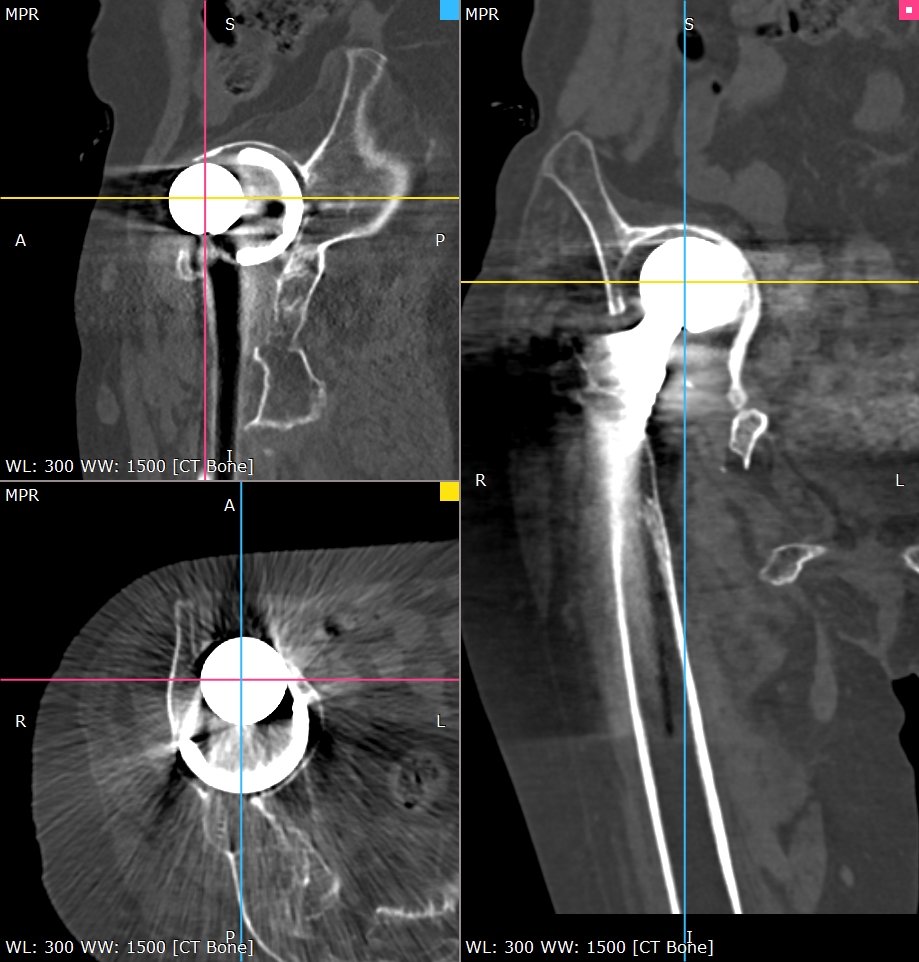

患者老年女性,类风湿性关节炎,骨质疏松,双侧全髋术后,髋臼假体移位至盆腔多年,不能行走。(The patient is an elderly female with rheumatoid arthritis and osteoporosis. After bilateral total hip surgery, the acetabular prosthesis has been displaced into the pelvic cavity for many years and she is unable to walk.)